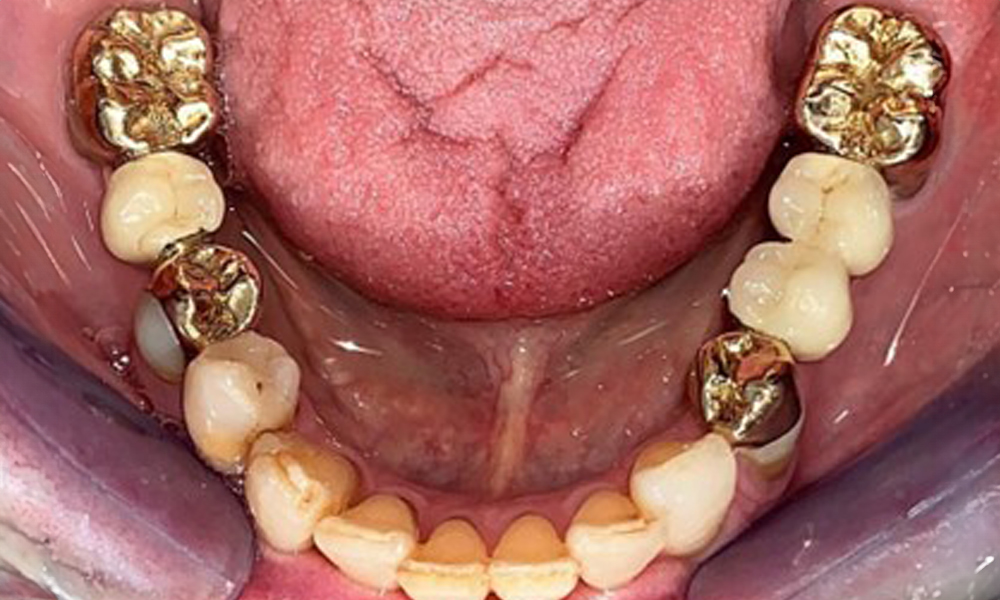

The patient was fitted with a combined removable maxillary telescopic prosthesis more than 25 years ago (Fig. 1, Fig. 2, Fig. 3) and is very happy with her dentures. The patient has an adequate fixed denture for the mandible (Fig. 4).

The dental findings are as follows: Combined removable implant and tooth-supported telescopic prostheses on implants 15, 13, 21, 23, 24, 25 and tooth 11 (Fig. 1, Fig. 2, Fig. 3). The patient was fitted with a fixed mandibular denture. Adequate bridges were present over 37 to 34 and 45 to 47 (Fig. 4), the crown margins were intact and there were no active caries. A composite filling with a marginal gap was present on tooth 43. There was mandibular gingival recession, exposing 1 to 3 mm of root surface. This also applies to 11.